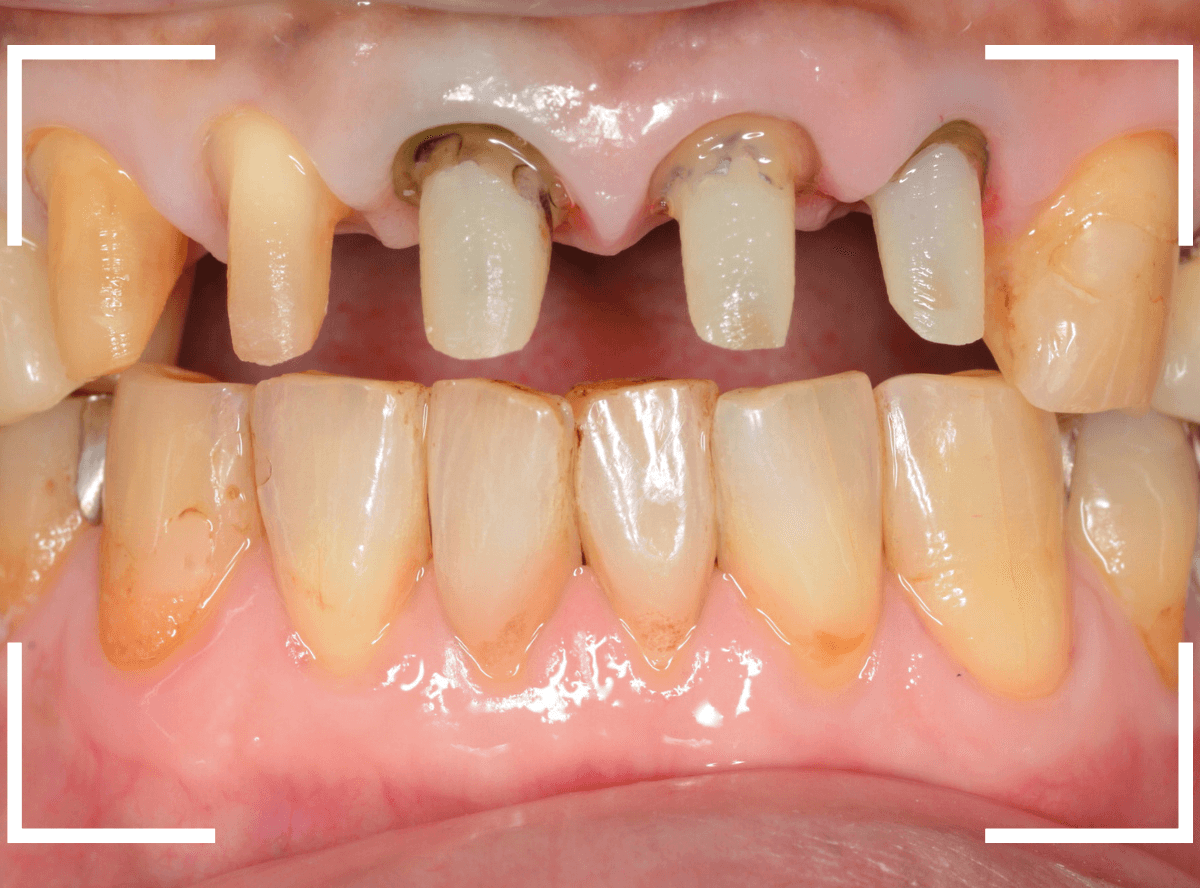

Case.15 上の前歯5本を一度にジルコニア・セラミックで治療したケース

今回は、前歯のさし歯が古くなったので、セラミックで綺麗にしたいというご希望の患者さんです。

患者さんのご希望は白い〇部分の3本でしたが、レントゲン検査をすると隣の2本も虫歯があり、一緒に治療をする事になりました。

左側の2本は虫歯を除去してみないと最終的にどのようにお治しするか何とも言えない状況でしたので、同時に治療しながら最終的な仕上げはご相談、となりました。

まず、前歯のさし歯を外します。

神経を取っている歯(無髄歯)ですので、痛みはありませんが、前後の2本は虫歯になっています。

これら、歯全体を覆うさし歯の中の虫歯はレントゲン写真でも写ってこないため、治療前に正確な判断ができません。

さし歯を外す時は、いつも想定外の虫歯などがないかどきどきします(><)

隣の歯の虫歯も顔を覗かせています。

虫歯を除去後に、裏側から撮影したところです。

思っていた以上に神経ギリギリ、歯全体に渡る大きな虫歯でした。

そのとなりの〇部の歯も同じように広くレジンをつめる治療をしてある中が大きな虫歯になっていました。

結局、5本ともさし歯で治療する必要がありましたので、審美性の高い、ジルコニア・セラミックで治療する事になりました。

治療前後の写真です。

やはり、上の前歯は大きく印象が変わりますね。